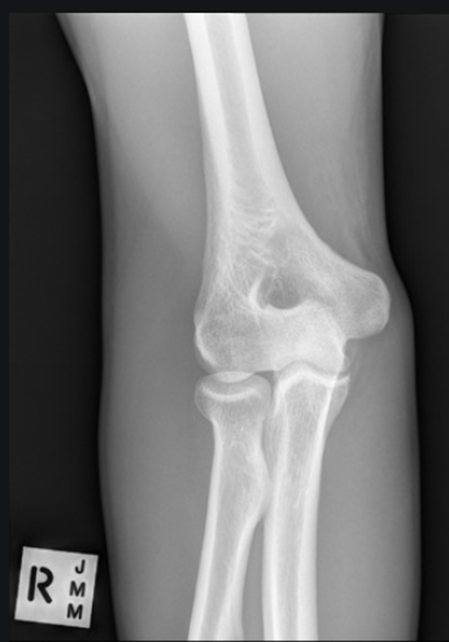

-All anatomy present (humerus, radius, and ulna)

-Only should be partial superimposition of the radius and ulna (this image they are fully separated)

-They are laterally rotated (fix by medially rotating them and feeling the epicondyles)

-Epicondyles not perfectly in profile (due to rotation)

-Olecranon in olecranon fossa

-Open Joint Space = pretty good

-No crowning of radial head (good)

• REPEAT

Critique this AP Elbow Image